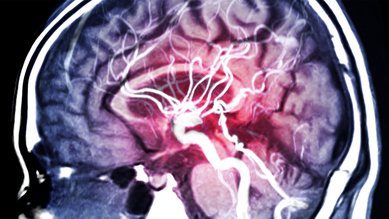

İnme

Bir inme meydana geldiğinde, beynin bir kısmına yeterince kan ulaşamaz. Bu hayati tehlike oluşturabilir. Ciddi sonuçları önlemek için hızlı tedavi önemlidir.

Beyin anevrizması

Beyin anevrizması, beyindeki bir arterde oluşan bir şişliktir. Genellikle fark edilmez ve bir şikayete neden olmaz. Beyin anevrizması patlarsa, ölüm tehlikesi arz eden bir beyin kanamasına neden olur.